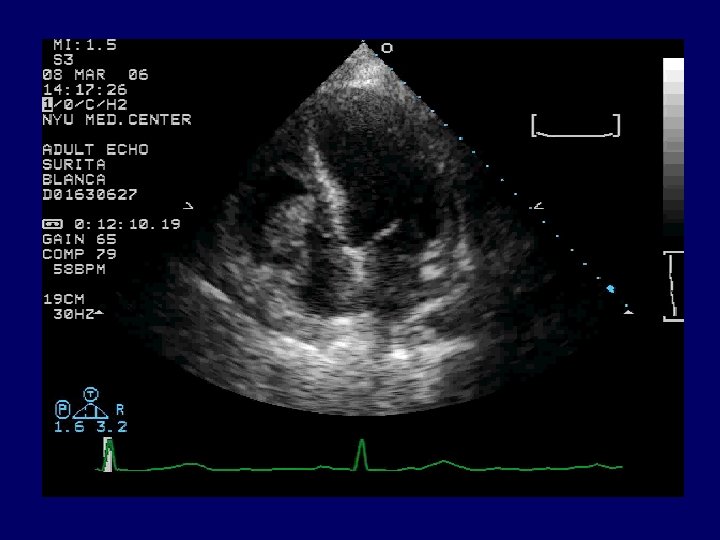

Radiology CXR: mild interstitial edema and cardiomegaly. Transthoracic echocardiogram (TTE): large 6. 5 x 2. 0 cm pedunculated mass attached to the lateral free wall of the right atrium separate from the tricuspid valve leaflets, with prolapse of the mass across the tricuspid valve and associated severe tricuspid insufficiency. A diagnostic procedure was performed…

Echocardiography